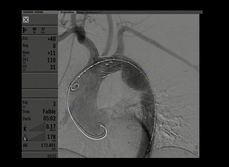

顱內(nèi)血管介入手術(shù)模塊

訓(xùn)練醫(yī)生進(jìn)行顱內(nèi)動脈瘤可脫彈簧圈栓塞術(shù)、顱內(nèi)動脈狹窄治療等手術(shù)操作